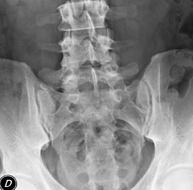

- Abdomen i pelvis

- RX Abdomen

Tècnica que usa els raigs X a través de la qual s'obtenen imatges de l'abdomen (estómac, intestí prim, intestí gros, fetge, ronyons, bufeta, pelvis òssia, etc.) per al seu estudi. - RX Columna lumbar

Tècnica que usa els raigs X a través de la qual s'obtenen imatges de la columna lumbar per al seu estudi. - TEGD (trànsit esòfag-gastro-duodenal)